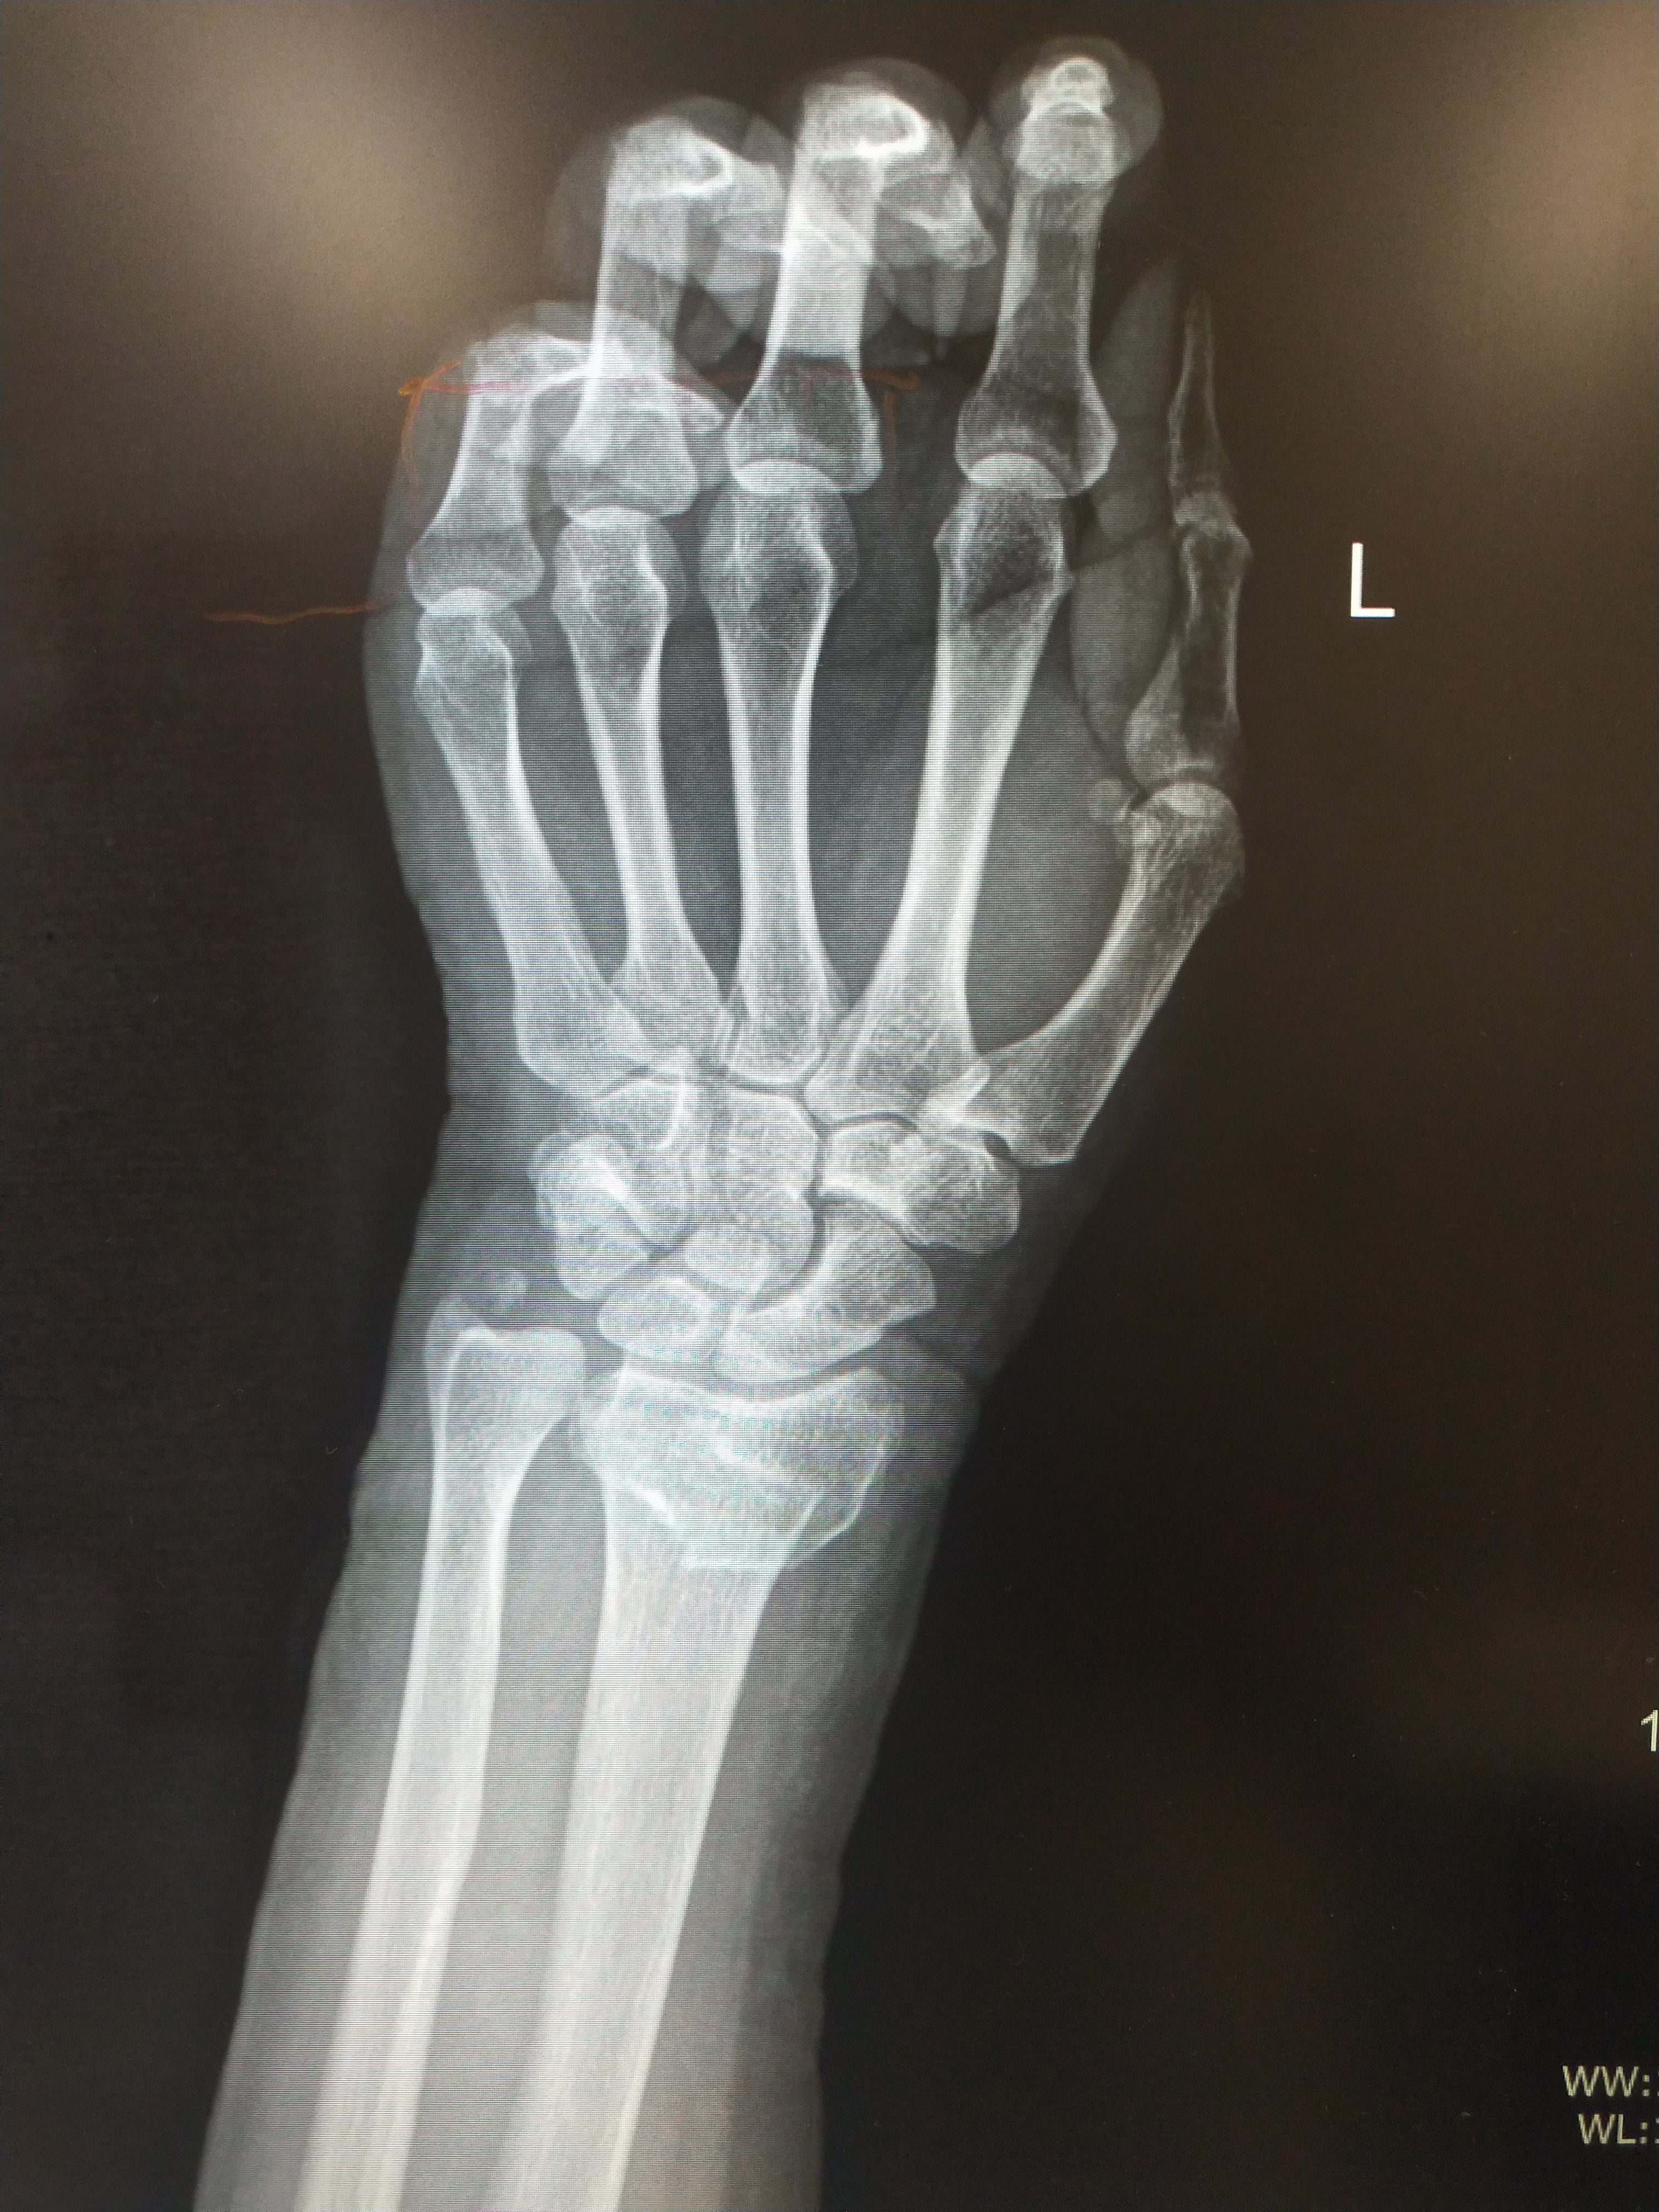

左腕关节ap与侧视的x射线图像库存照片 图片包括有左腕关节ap与侧视的x射线图像

左腕关节ap与侧视的x射线图像库存图片 图片包括有左腕关节ap与侧视的x射线图像